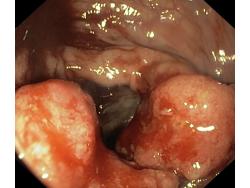

Nowotwory przewodu pokarmowego